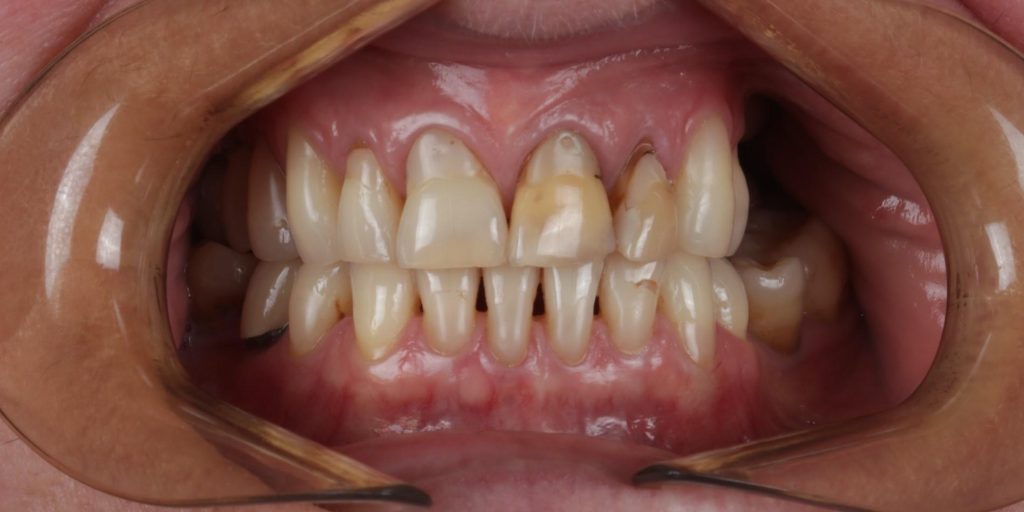

Pierwszy etap to kompleksowa konsultacja u dr Joanny Zawirskiej-Poły. Podczas tej wizyty zostało wykonane badanie przedmiotowe, podmiotowe, badanie mięśni i stawów, analiza okluzji, badanie stomatologiczne, tomografia komputerowa, rejestracja fotograficzna i długa rozmowa z Pacjentką na temat jej oczekiwań.

Pacjentka, zgłaszając się już na kolejną wizytę świadomie podjęła opcję pośrednią z proponowanych działań: wyleczenie zębów zachowawczo, endodontycznie z zabezpieczeniem protetycznym, estetyczne korekty uśmiechu licówkami, ćwierćkoronami i koronami, jednak bez pełnej przebudowy zwarcia (z zachowaniem starszych odbudów w strefach bocznych, które były wykonane na implantach w przeszłości), która jest zawsze najbardziej polecana, odtwarza prawidłowe kontakty, a także umożliwia lekarzowi i technikowi najlepsze warunki do nadania odpowiednich i harmonijnych kształtów. Te wszystkie działania chronią na przyszłość staw skroniowo-żuchwowy.

Pomimo zaleceń dr do wdrożenia również leczenia ortodontycznego, Pacjentka, znając wszystkie wady i zalety bezwzględnie zdecydowana zakamuflować stłoczenia, nieprawidłowości kontaktów, płaszczyzny zgryzowe, tylko i wyłącznie protetycznymi rozwiązaniami. Dr Joanna ustaliła z Pacjentką pod Jej wymagania wspólny plan działań. Wybierając takie rozwiązanie lekarz i laboratorium ma zawsze utrudnienie, by jaknajbardziej harmonijnie zaplanować projekt uśmiechu.